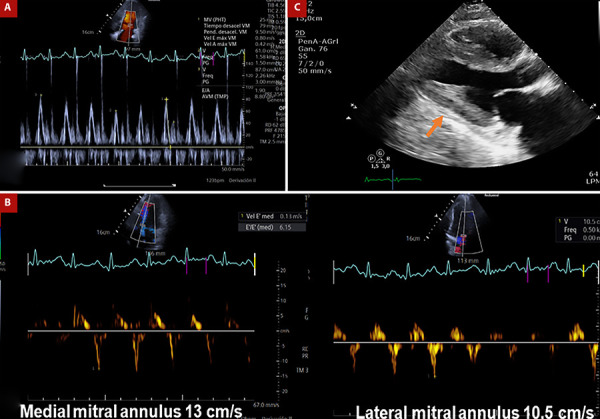

Constrictive pericarditis (CP) is an infrequent complication following heart transplantation (HTx) and arises from diverse postoperative occurrences, including mediastinitis, pericardial effusion, or allograft rejection. Indeed, this rare clinical entity can be misdiagnosed as a rejection episode or restrictive cardiomyopathy. In this report, we present the case of a 43-year-old male who underwent HTx 1.5 years prior and was subsequently admitted to our center due to the gradual onset of symptoms indicative of right congestive heart failure, with an initial diagnosis of constrictive pericarditis.